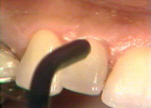

| Esta serie de

imágenes muestra el diagnóstico y tratamiento de la periodontitis

moderada en una mujer de 35 años de edad. Se observa

inflamación por el cambio de color, aspecto de la superficie y por la consistencia del margen gingival. Si el margen

gingival está flojo cuando aplicamos aire de la jeringa triple es una indicación de inflamación

del tejido. |

Se sondea las

bolsas periodontales en bucal, mesial, distal y palatino. Observandose

la profundidad y registramos el sangrado si lo hubiere. La destrucción del

periodonto es generalmente irregular y es necesario mover la punta de la sonda en varias direcciones para encontrar el sitio más profundo

en cada superficie. |

Note la

inflamación gingival y la presencia de placa supragingival en los

dientes. En bucal del segundo molar hay una bolsa profunda al

sondaje y placa supra y subgingival al movimiento lateral de la sonda. |